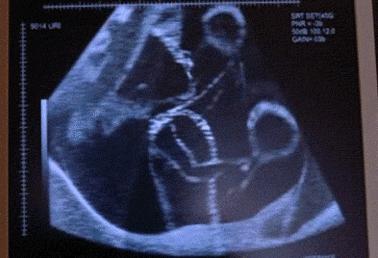

宝宝第一次胎动的感觉可能还历历在目,但转眼间,他就要出生了。宝宝在孕晚期的胎动方式变化多样,学会如何数胎动有助于你判断宝宝的健康状况,特别是如果你是高危孕妇的话。

从怀孕28周开始,宝宝的生活节奏就比较有规律了。宝宝醒着时的胎动多,幅度大;而睡着后就比较安静,即使有胎动,幅度也很小。宝宝在怀孕28周之后的胎动会发生的变化为:

宝宝在临产前会进入你的骨盆,做好出生的准备。由于空间变小,羊水逐渐减少,宝宝的大幅度胎动也就随之减少了。但你会感觉到宝宝在你的肋骨下面不规律的踢腿,如果你的腹壁较薄,甚至可以在胎动时,在你的腹部触到宝宝的小脚小手。